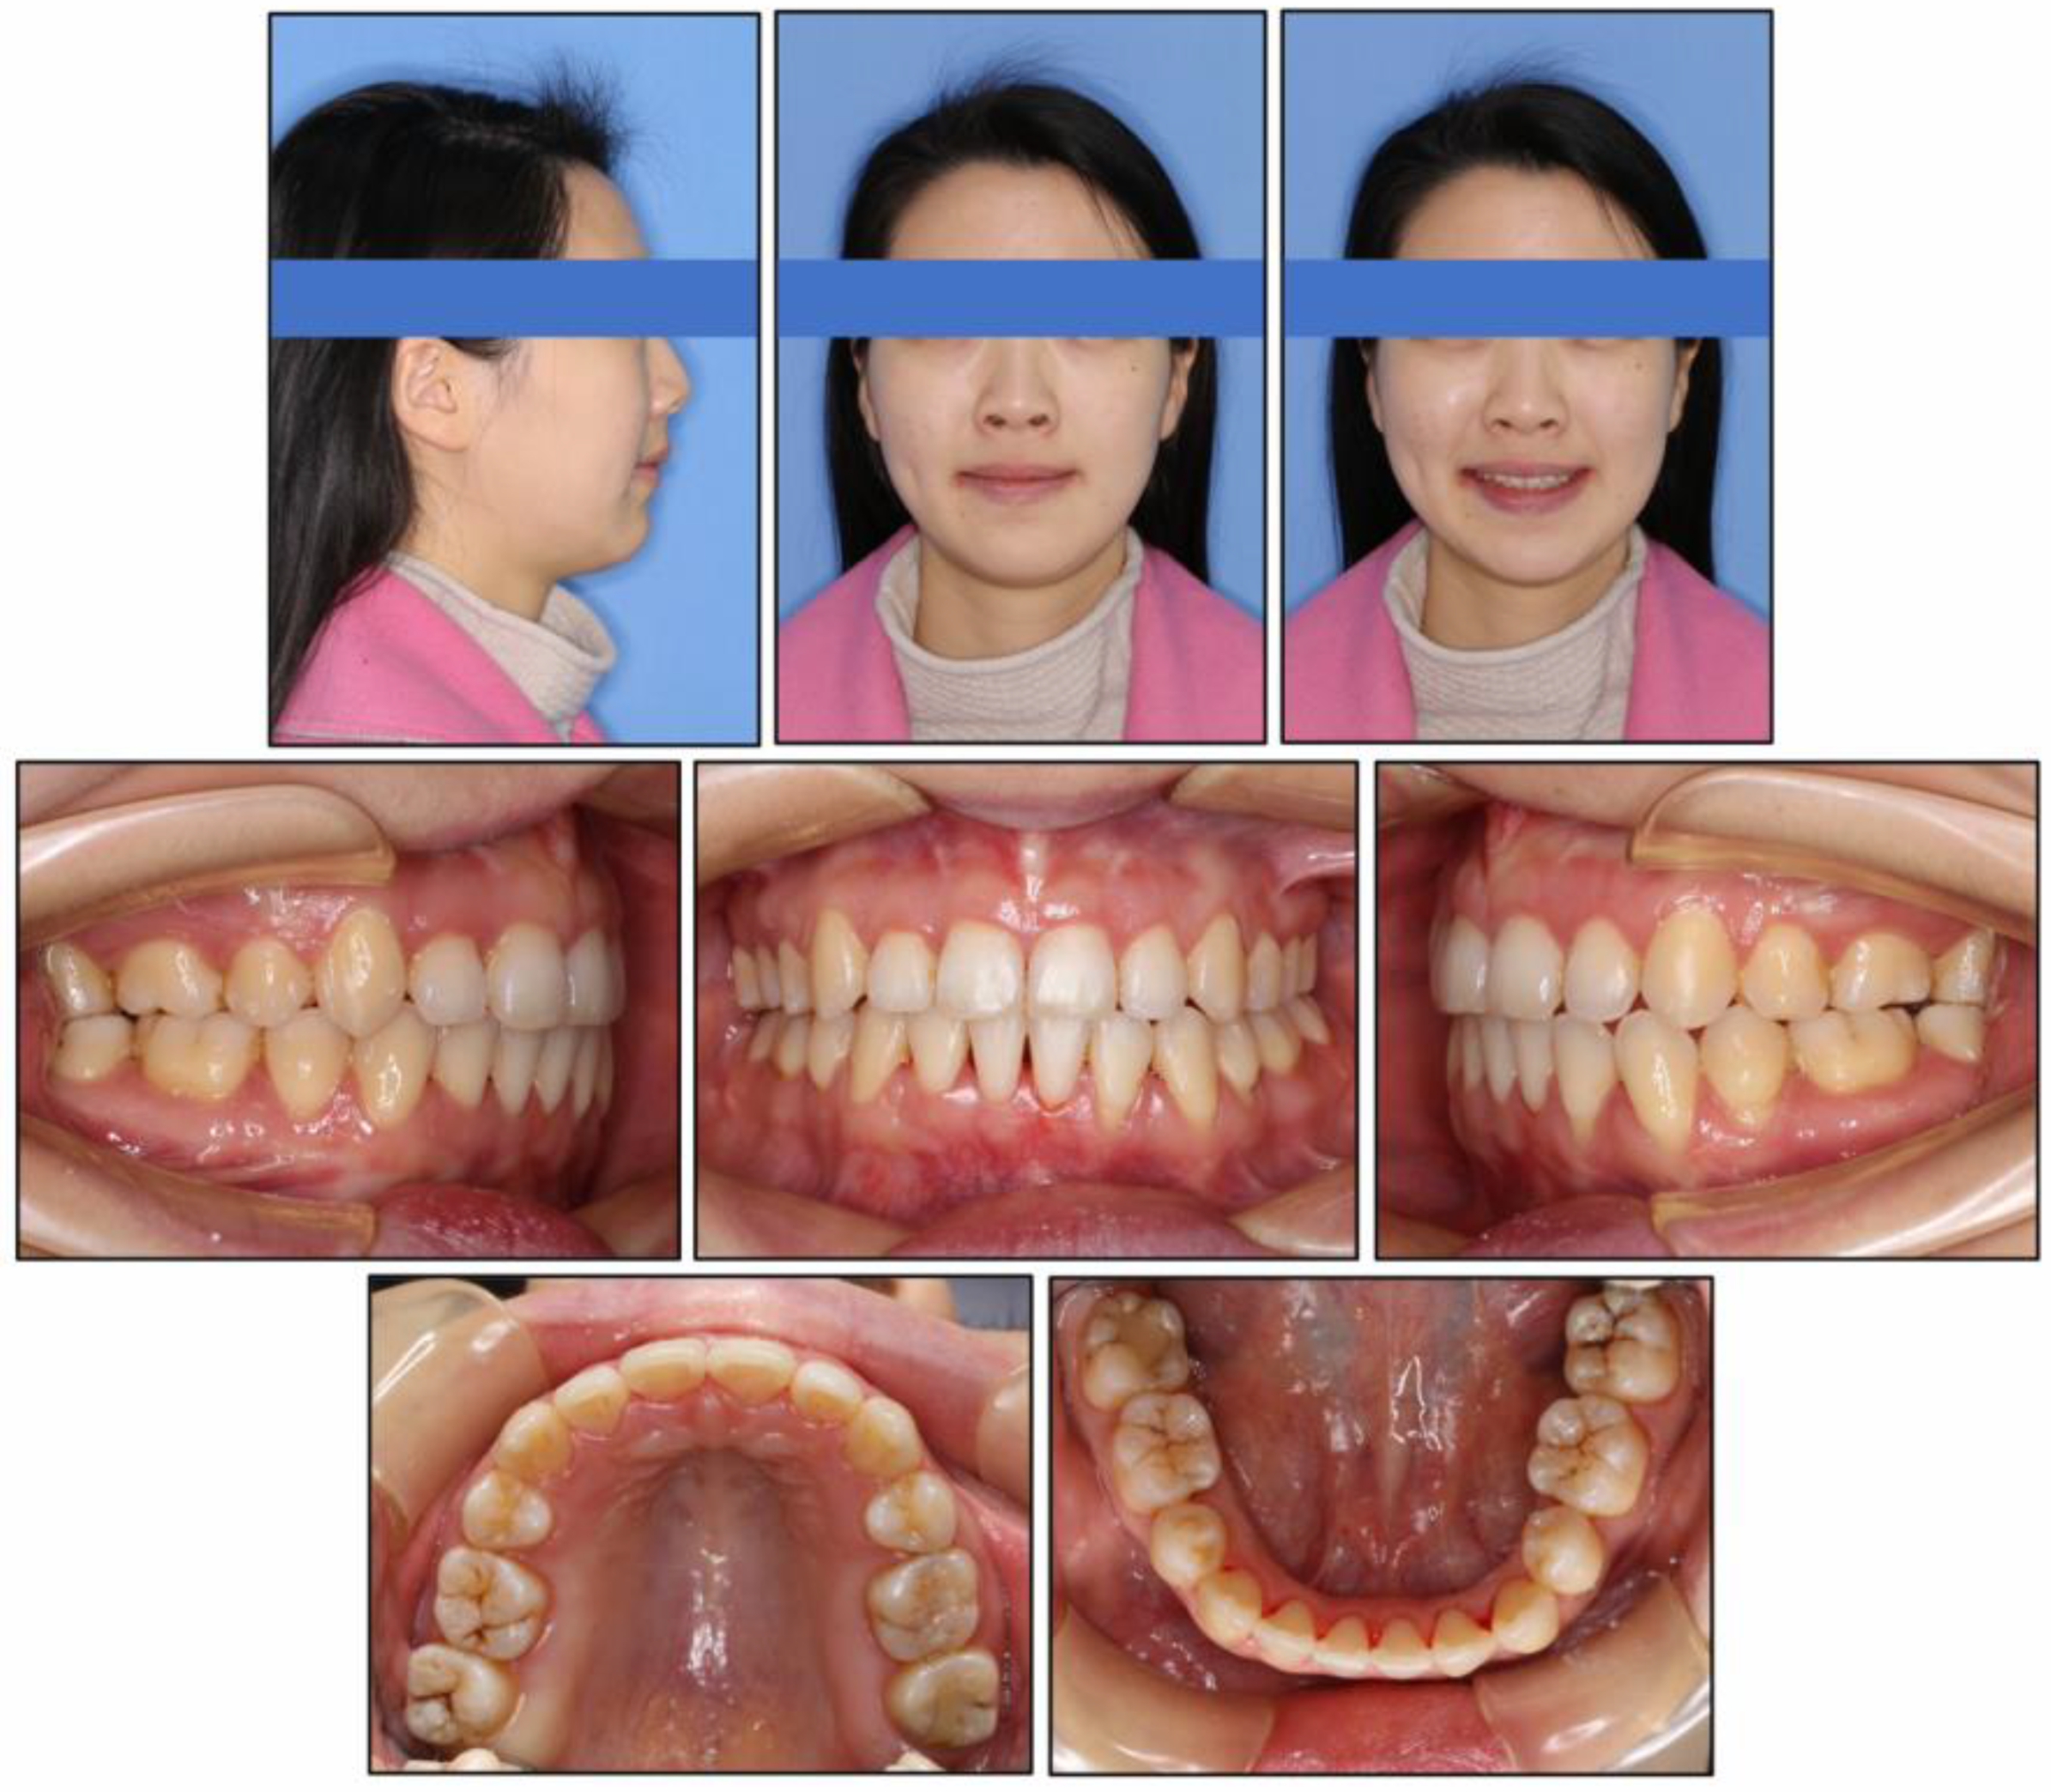

2.5. Treatment Results

| SNA (°) | 83.1 ± 2.7 | 80.3 | 79.7 | −0.6 |

| SNB (°) | 80.3 ± 2.6 | 71.9 | 73.9 | 2 |

| ANB (°) | 2.7 ± 1.8 | 8.4 | 5.8 | −2.6 |

| UI-SN (°) | 103.4 ± 5.5 | 106.9 | 91.9 | −15 |

| LI-MP (°) | 96.3 ± 5.4 | 97.2 | 90.8 | −6.4 |

| UI-LI (°) | 129.1 ± 7.1 | 102.7 | 129.1 | 26.4 |

| MP-SN (°) | 32.6 ± 6.9 | 55.8 | 52.9 | −2.9 |

| MP-FH (°) | 25.5 ± 4.8 | 45.6 | 42.8 | −2.8 |

| Wits (mm) | −1 ± 1 | 5.8 | 2.8 | −3 |

| A-OP (°) | 10 ± 3.58 | 12.2 | 14.5 | 2.3 |

| P-OP (°) | 14.9 ± 3.85 | 25.1 | 16.2 | −8.9 |

| U1-PP (mm) | 28 ± 1.6 | 32.9 | 26.6 | −6.3 |

| U6-PP (mm) | 23 ± 1 | 24.4 | 19.3 | −5.1 |

| L1-MP (mm) | 40.8 ± 1.8 | 44.1 | 39.3 | −4.8 |

| L6-MP (mm) | 31.1 ± 1.9 | 33.4 | 28.9 | −4.5 |

| Palatal-OP (°) | 10 ± 4 | 17 | 15.7 | −1.3 |

| Upper Face Height (mm) | 50 ± 2.5 | 56.4 | 55.8 | −0.6 |

| Lower Face Height (mm) | 65 ± 4.5 | 81.1 | 75.4 | −5.7 |

| Anterior Face Height (mm) | 115 ± 5.5 | 135.9 | 130.8 | −5.1 |

| Posterior Face Height (mm) | 45 ± 5 | 75.9 | 73.2 | −2.7 |

| P-A Face Height (%) | 65 ± 4 | 55.8 | 56 | 0.2 |

| Y-Axis (°) | 67 ± 5.5 | 84.7° | 83.1 | −1.6 |

| UL-E (mm) | −1.6 ± 1.5 | 5 | −1 | −6 |

| LL-E (mm) | −0.2 ± 1.9 | 7 | −1.3 | −8.3 |